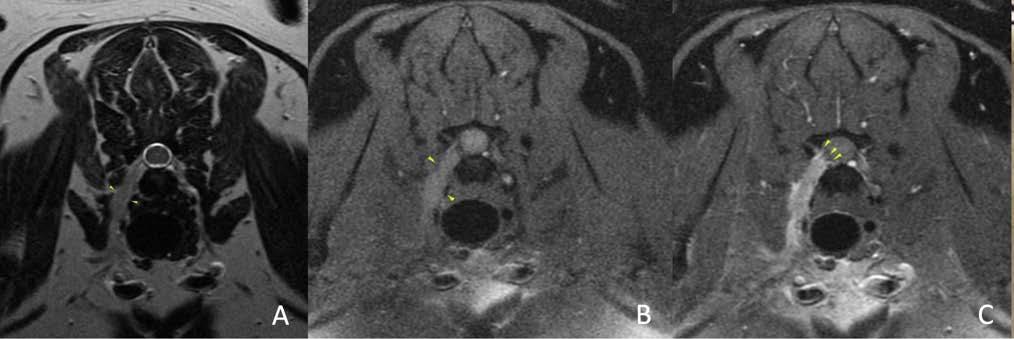

Se procedió a realizar una TC de cráneo (posicionamiento en recumbencia esternal, con 1,25 mm de corte, adquiriendo imágenes pre y postcontraste con contraste yodado Iohexol (Omnipaque 300 mg/ ml, GE Healthcare Bio-Sciences, Florida) 400 mg/kg, con algoritmo de reconstrucción de tejido blando y hueso, General Electrics Healthcare, 4 cortes, España, Madrid). En la TC se observó en la cavidad nasal izquierda una moderada destrucción de turbinetes nasales con severo engrosamiento de la mucosa nasal y presencia de tejido blando anómalo (Fig. 1A), sin presencia de masas o cuerpos extraños, ni afectación de la lámina cribiforme. Dichas lesiones se extendían al seno frontal izquierdo (Fig. 1B). A continuación, se realizó una rinoscopia (fibroscopio 5,9 mm, FujiFilm, España, Madrid) donde se observó en la cavidad nasal izquierda múltiples placas de color blanquecino con aspecto caseoso/algodonoso adheridas a la mucosa nasal con eritema y congestión asociados (Fig. 2), junto a la destrucción moderada de los turbinetes, mostrando un aspecto cavitado. La cavidad nasal derecha no presentó alteraciones. Se tomaron muestras de tejido (placa fúngica y mucosa adyacente) para cultivo y análisis histopatológico. En el cultivo se obtuvo un crecimiento de Aspergillus fumigatus, y en los resultados de la biopsia de la placa fúngica se observó un tejido eosinofílico con abundantes hifas septadas, mientras que en el tejido adyacente se evidenció una mucosa erosionada y ulcerada con abundantes neutrófilos y macrófagos con hifas fúngicas esporádicas. Como terapia se optó por la aplicación tópica intranasal de una pomada depot de clotrimazol 1 %

1. (A) Imagen de la TC de cráneo (región nasal, corte transversal en ventana de hueso postcontraste). Se observa una diferencia evidente entre la cavidad nasal derecha e izquierda, con moderada pérdida y destrucción de los turbinetes junto al engrosamiento de la mucosa y la presencia de tejido blando anómalo de la cavidad nasal izquierda (flecha azul). (B) Imagen de la TC de cráneo (región frontoorbitaria, corte transversal en ventana de hueso postcontraste). Se evidencia la presencia de engrosamiento de la mucosa y de tejido blando anómalo ubicado en el seno frontal izquierdo (flecha roja).

Los hallazgos más comunes de la TC son la destrucción de los cornetes nasales y ausencia del laberinto etmoidal, junto a la presencia de tejido blando anómalo y engrosamiento de la mucosa adyacente, pudiendo extenderse a los senos (72-74 %). En casos graves puede presentar reacción ósea y lisis de la lámina cribiforme.1,2 Estas lesiones no son específicas, pudiendo presentarse hallazgos similares en otras patologías (p. ej., rinitis linfoplasmocitaria).2 La TC también permite valorar la presencia de causas predisponentes (cuerpos extraños, neoplasias, fracturas), además de la afectación de los senos y la presencia de afectación de la lámina cribiforme.1,2,5 En el presente caso se observaron alteraciones compatibles, llegando a afectar al seno frontal izquierdo, pero no presentaba una severa destrucción de los cornetes ni afectación de la lámina; posiblemente, la enfermedad estuviera en una fase temprana.